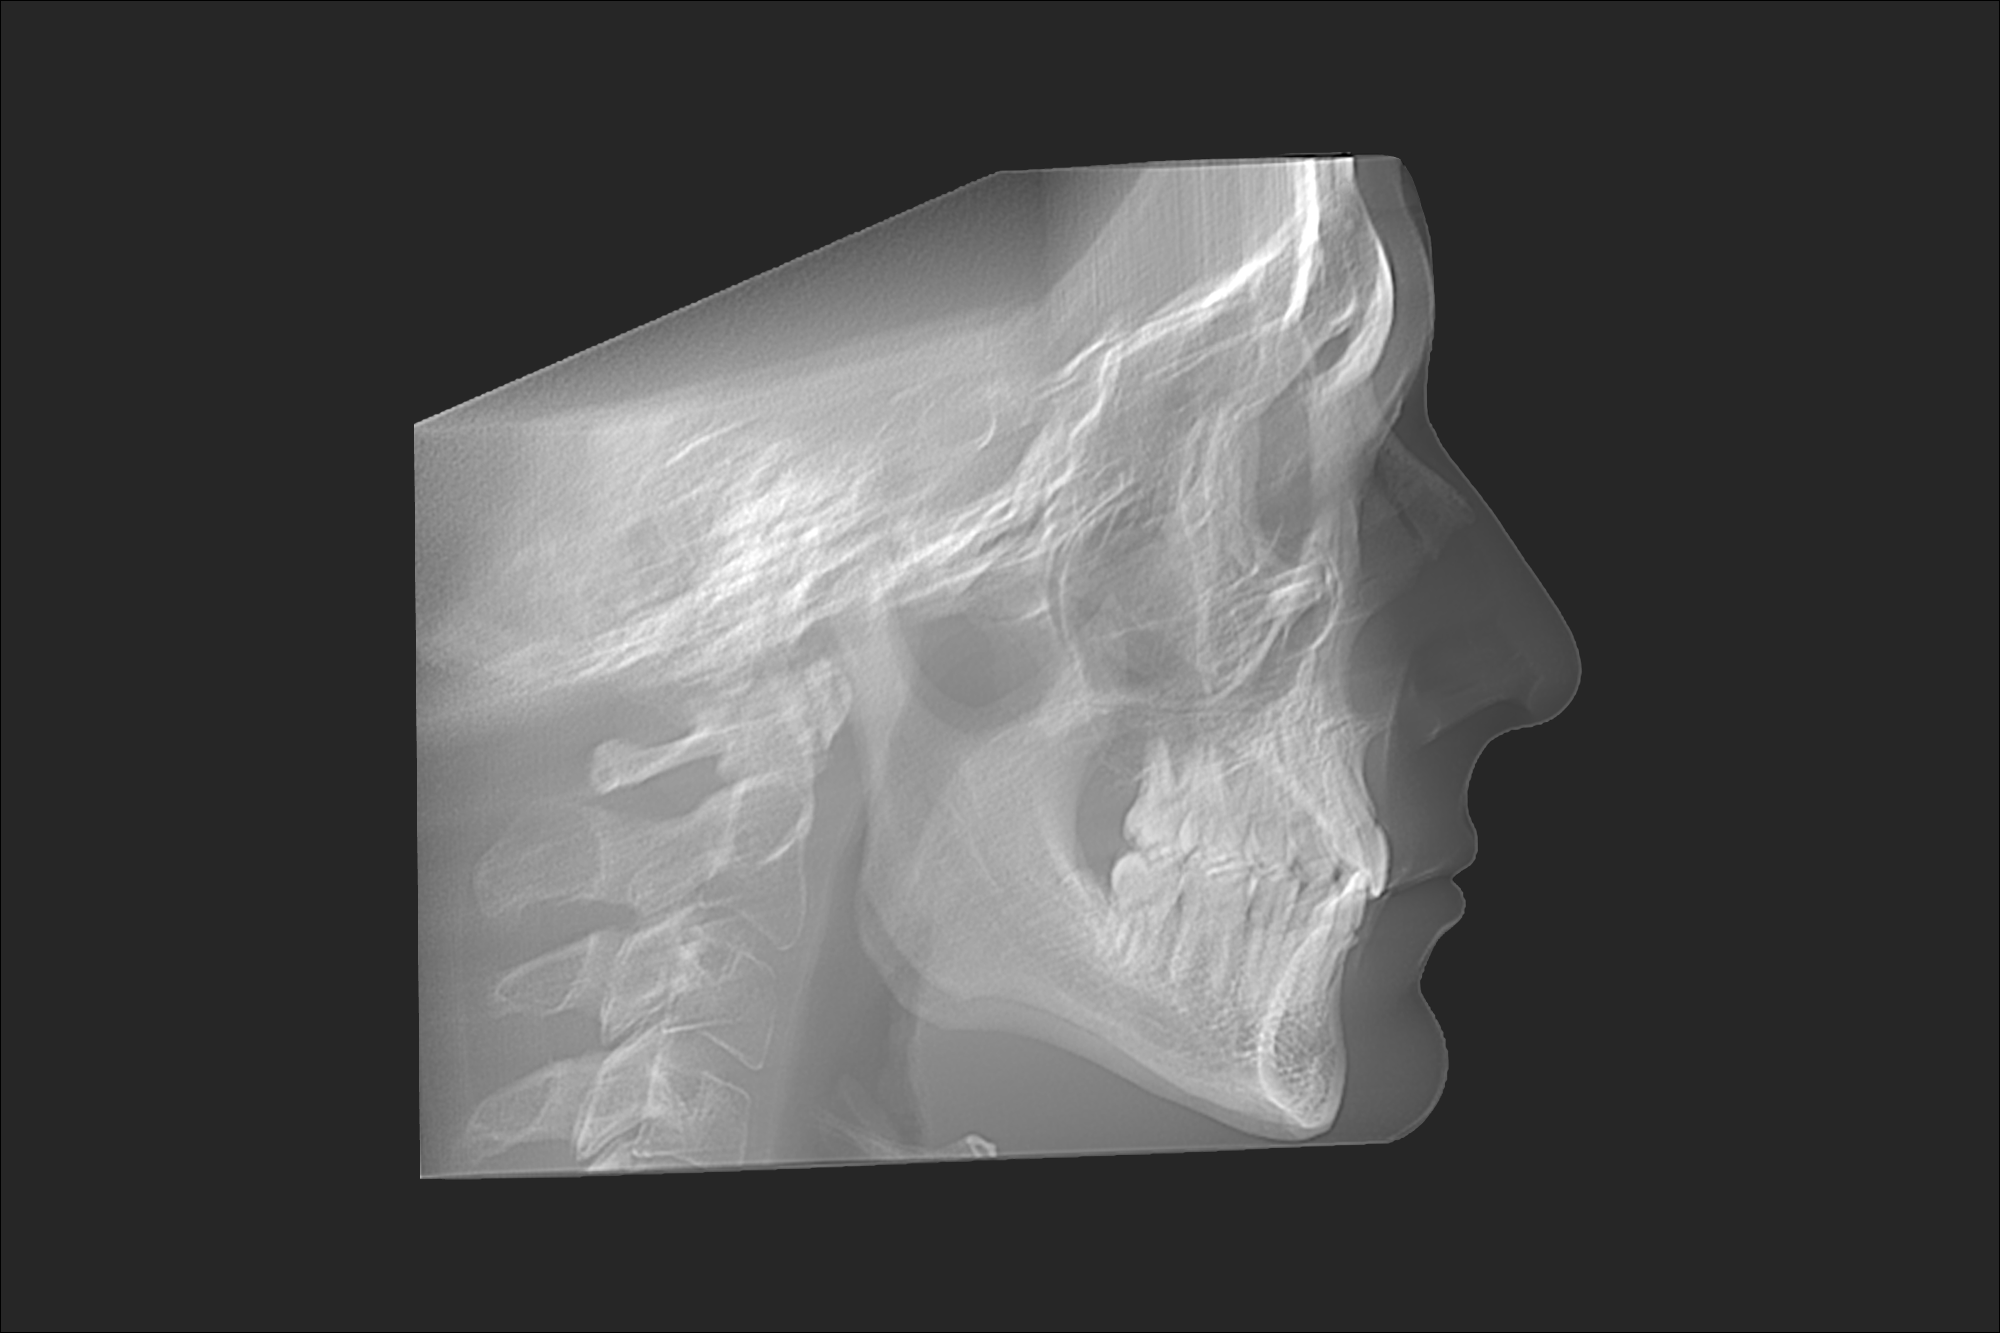

Your evaluation includes a CT scan, comprehensive oral images, sleep assessment, and personalized treatment plan from Dr. Trivedi. If you choose to proceed with the complete solution stack, your evaluation costs will be applied as a discount.

After your evaluation, the doctor reviews your results and explains how your airway structures are impacting your health. You’ll then receive a personalized plan that may include palatal expansion, aligners, or other therapies to optimize your health.